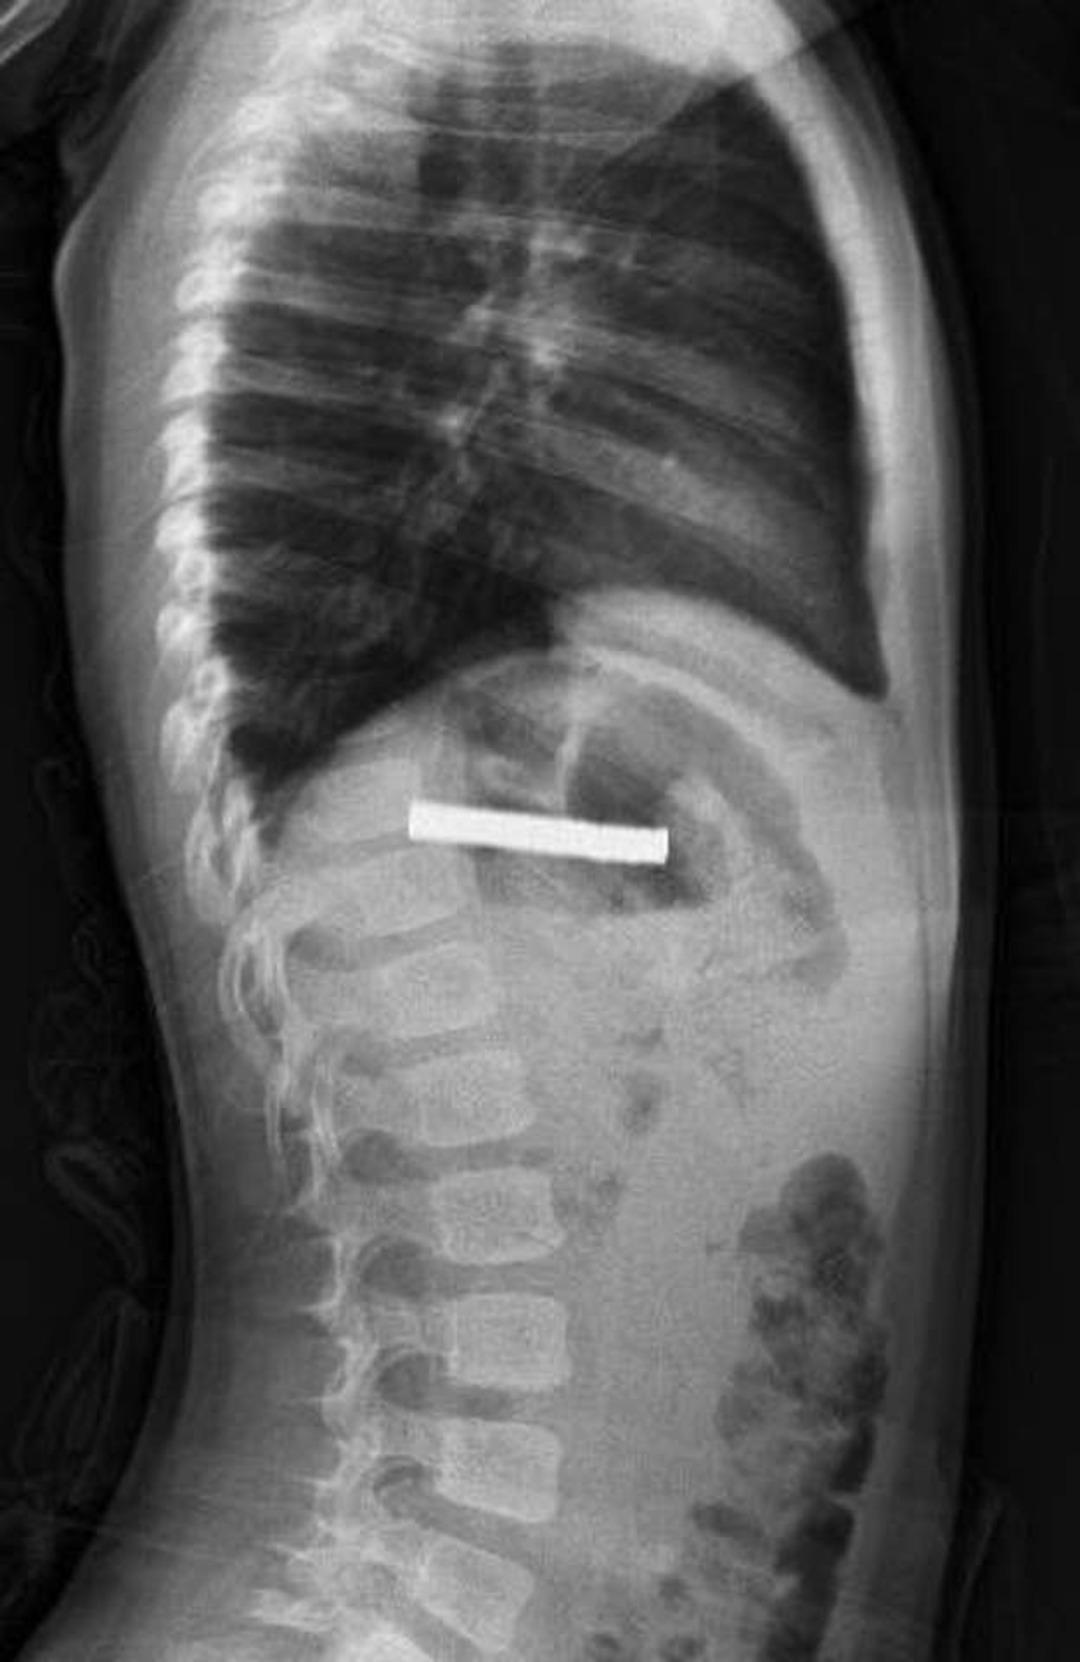

Fırat Üniversitesi Çocuk Gastroenteroloji Hepatoloji ve Beslenme Bilim Dalı Başkanı Prof. Dr. Yaşar Doğan, çocuk hastanın yemek borusuna yapışmış 19 mıknatısı endoskopik yöntemle çıkardı.

Mıknatıslar uzun süre yemek borusunda takılı kaldığı için yemek borusu ve mide girişinde zedelenmeler olurken, çocuğun sağlık durumunun iyi olduğu ve taburcu edildiği öğrenildi.